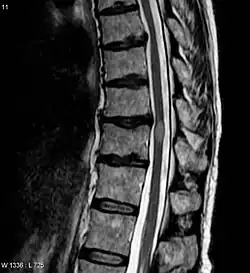

| Acute myelitis | intramedullary lesion > 3 contiguous segments, or spinal atrophy ≥ 3 contiguous segments |

In NMOSD, areas of brain tissue that appear normal in conventional magnetic resonance imaging (MRI) can show damage in diffusion tensor imaging (DTI), although less so compared to multiple sclerosis (MS).[25]

The most common initial manifestation of the disease is inflammation of the spinal cord (myelitis).[4] Myelitis causes spinal cord dysfunction, which can result in muscle weakness, paralysis in the limbs, lost or reduced sensation, spasms, loss of bladder and bowel control, or erectile dysfunction.[1][4][2][7][8][9] The myelitis can be transverse, affecting an entire cross-section of the spinal cord, and showing bilateral symptoms.

The clinical course and the response to therapy is different for various diseases classed within these groups, showing a better prognosis for those in the NMO-Ab(−)/MOG-Ab(−) group, and a worse prognosis for those in the NMO-Ab(+)/MOG-Ab(+) group.[30] The MOG-related NMO can be radiologically identified by the conus involvement. Myelin-oligodendrocyte glycoprotein antibody–positive patients were more likely to have conus involvement on spinal magnetic resonance imaging.[31]